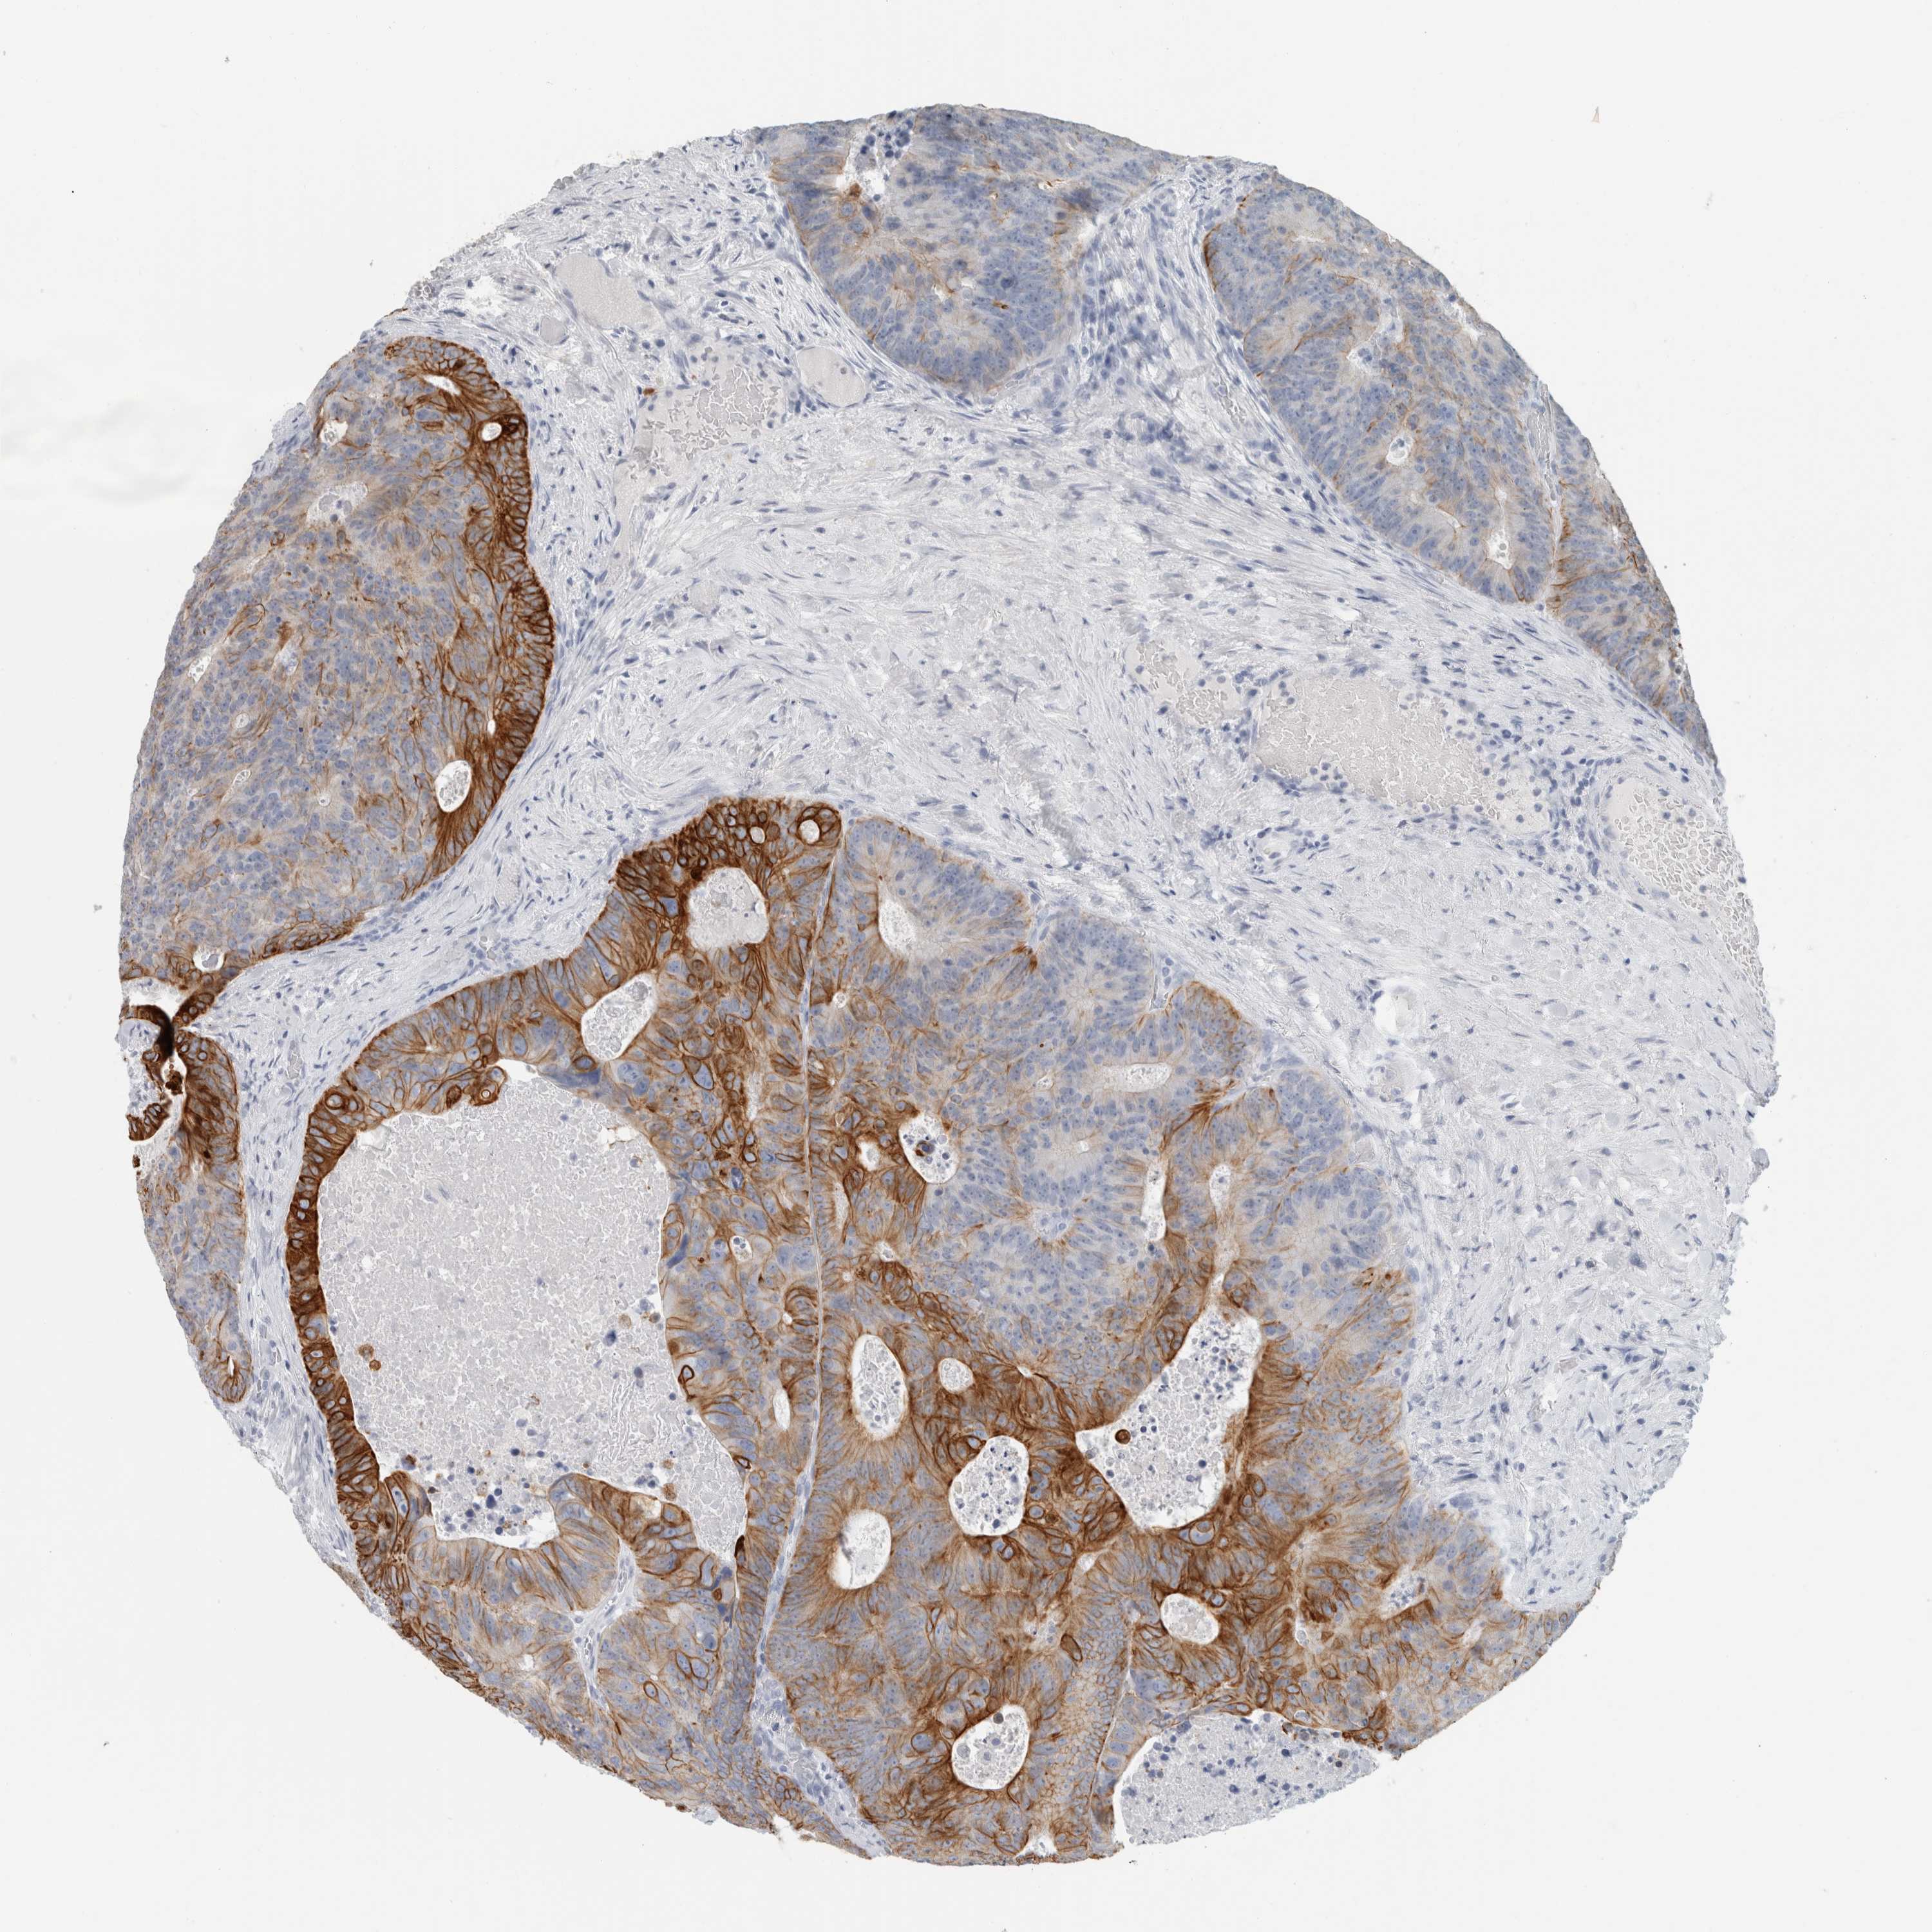

CANCER COLORECTAL CANCER Show tissue menu

Colorectal cancer

Human cancer

Colon adenocarcinoma